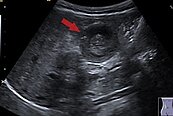

間歇性腹痛小心「腸套疊」惹禍!好發族群介於「這年齡層」 2023/08/31 14:30 一名1歲的小男嬰,在睡覺前突然躁動不安,小孩無法入睡也無法被安撫,所以焦急的媽媽帶著男嬰來急診求助。小孩並沒有發燒,也沒有任何呼吸道、腸胃道症狀,在診間當下的精神狀態... 居家 男嬰 腺病毒 腸胃道 腸套疊 人氣: 81